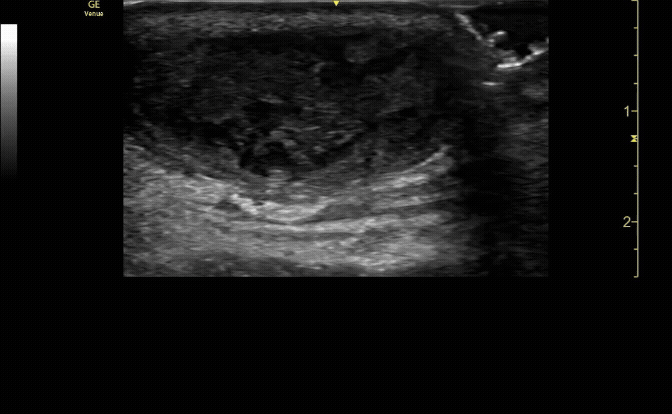

Extensor tenosynovitis in a patient following a cat bite.

Necrotizing fasciitis. Note air under the tendon.